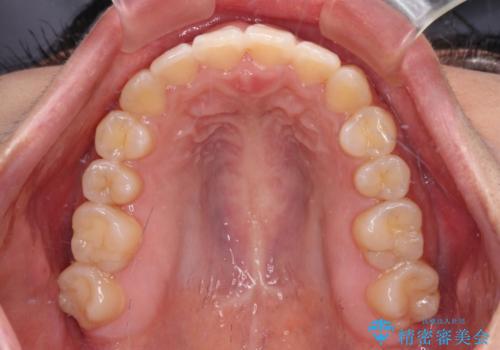

- 上下の前歯が非接触であることと、それに伴う口元の閉じにくさを気にして来院された患者様です。

奥歯の咬み合わせを見ると、上顎が下顎に対して相対的に前方にありました。

口元の閉じにくさを改善するためには、上顎臼歯を後方に移動させた咬み合わせにする必要があります。

インビザライン単体で改善することも可能ですが、達成する可能性が高くないため、カリエールディスタライザーという補助装置を併用して、より確実性を上げることとしました。

奥歯の咬み合わせを改善しながら、並行してインビザラインで歯列を整えることとしました。

カリエールディスタライザーを併用したことで、確実かつ短期間で治療を終えることができました。